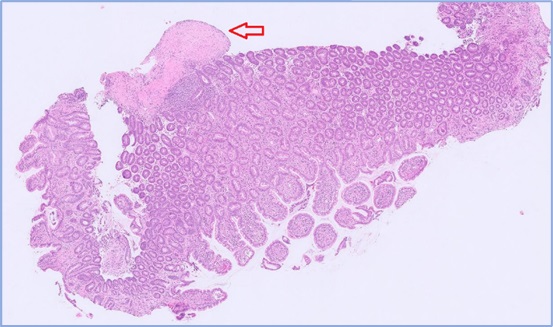

Full-thickness samples: These are the best samples to send if you are concerned about neoplasia or if there is suspicion of lesions in the submucosa or muscular wall. Many lesions are within the deep mucosa, crypts or submucosa so superficial samples may not be diagnostic. Adenocarcinoma of the GIT is often diagnosed based on invasive lesions in the submucosa or wall – endoscopic samples limited to the mucosa may miss the lesion (see Fig. 3, an example of invasive rectal adenocarcinoma).

Fig 3. Rectal adenocarcinoma in a dog.